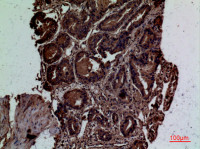

IHC-P analysis of human lung adenocarcinoma tissue using GTX79146 ALK (phospho Tyr1586) antibody.